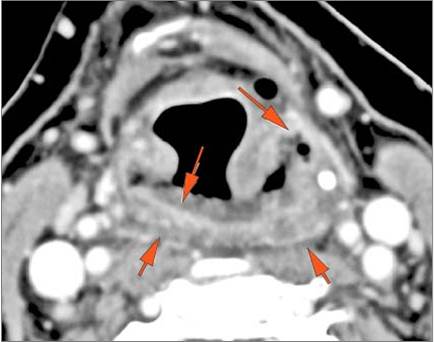

There is edema or abscess within in the hypopharynx, larynx or trachea. [Yes/No]

There is edema or abscess within the adjacent parapharyngeal and retropharyngeal spaces. [Yes/No]